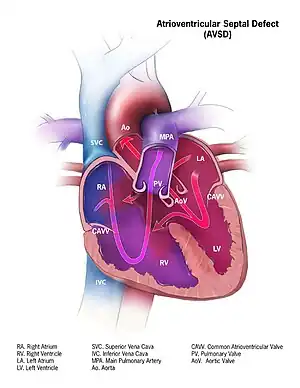

| Illustration of a atrioventricular septal defect | |

Atrioventricular septal defect (AVSD) is characterized by a deficiency of the atrioventricular septum of the heart. It is caused by an abnormal or inadequate fusion of the superior and inferior endocardial cushions with the mid portion of the atrial septum and the muscular portion of the ventricular septum.

If there is a defect in the septum, it is possible for blood to travel from the left side of the heart to the right side of the heart, or the other way around. Since the right side of the heart contains venous blood with a low oxygen content, and the left side of the heart contains arterial blood with a high oxygen content, it is beneficial to prevent any communication between the two sides of the heart and prevent the blood from the two sides of the heart from mixing with each other.